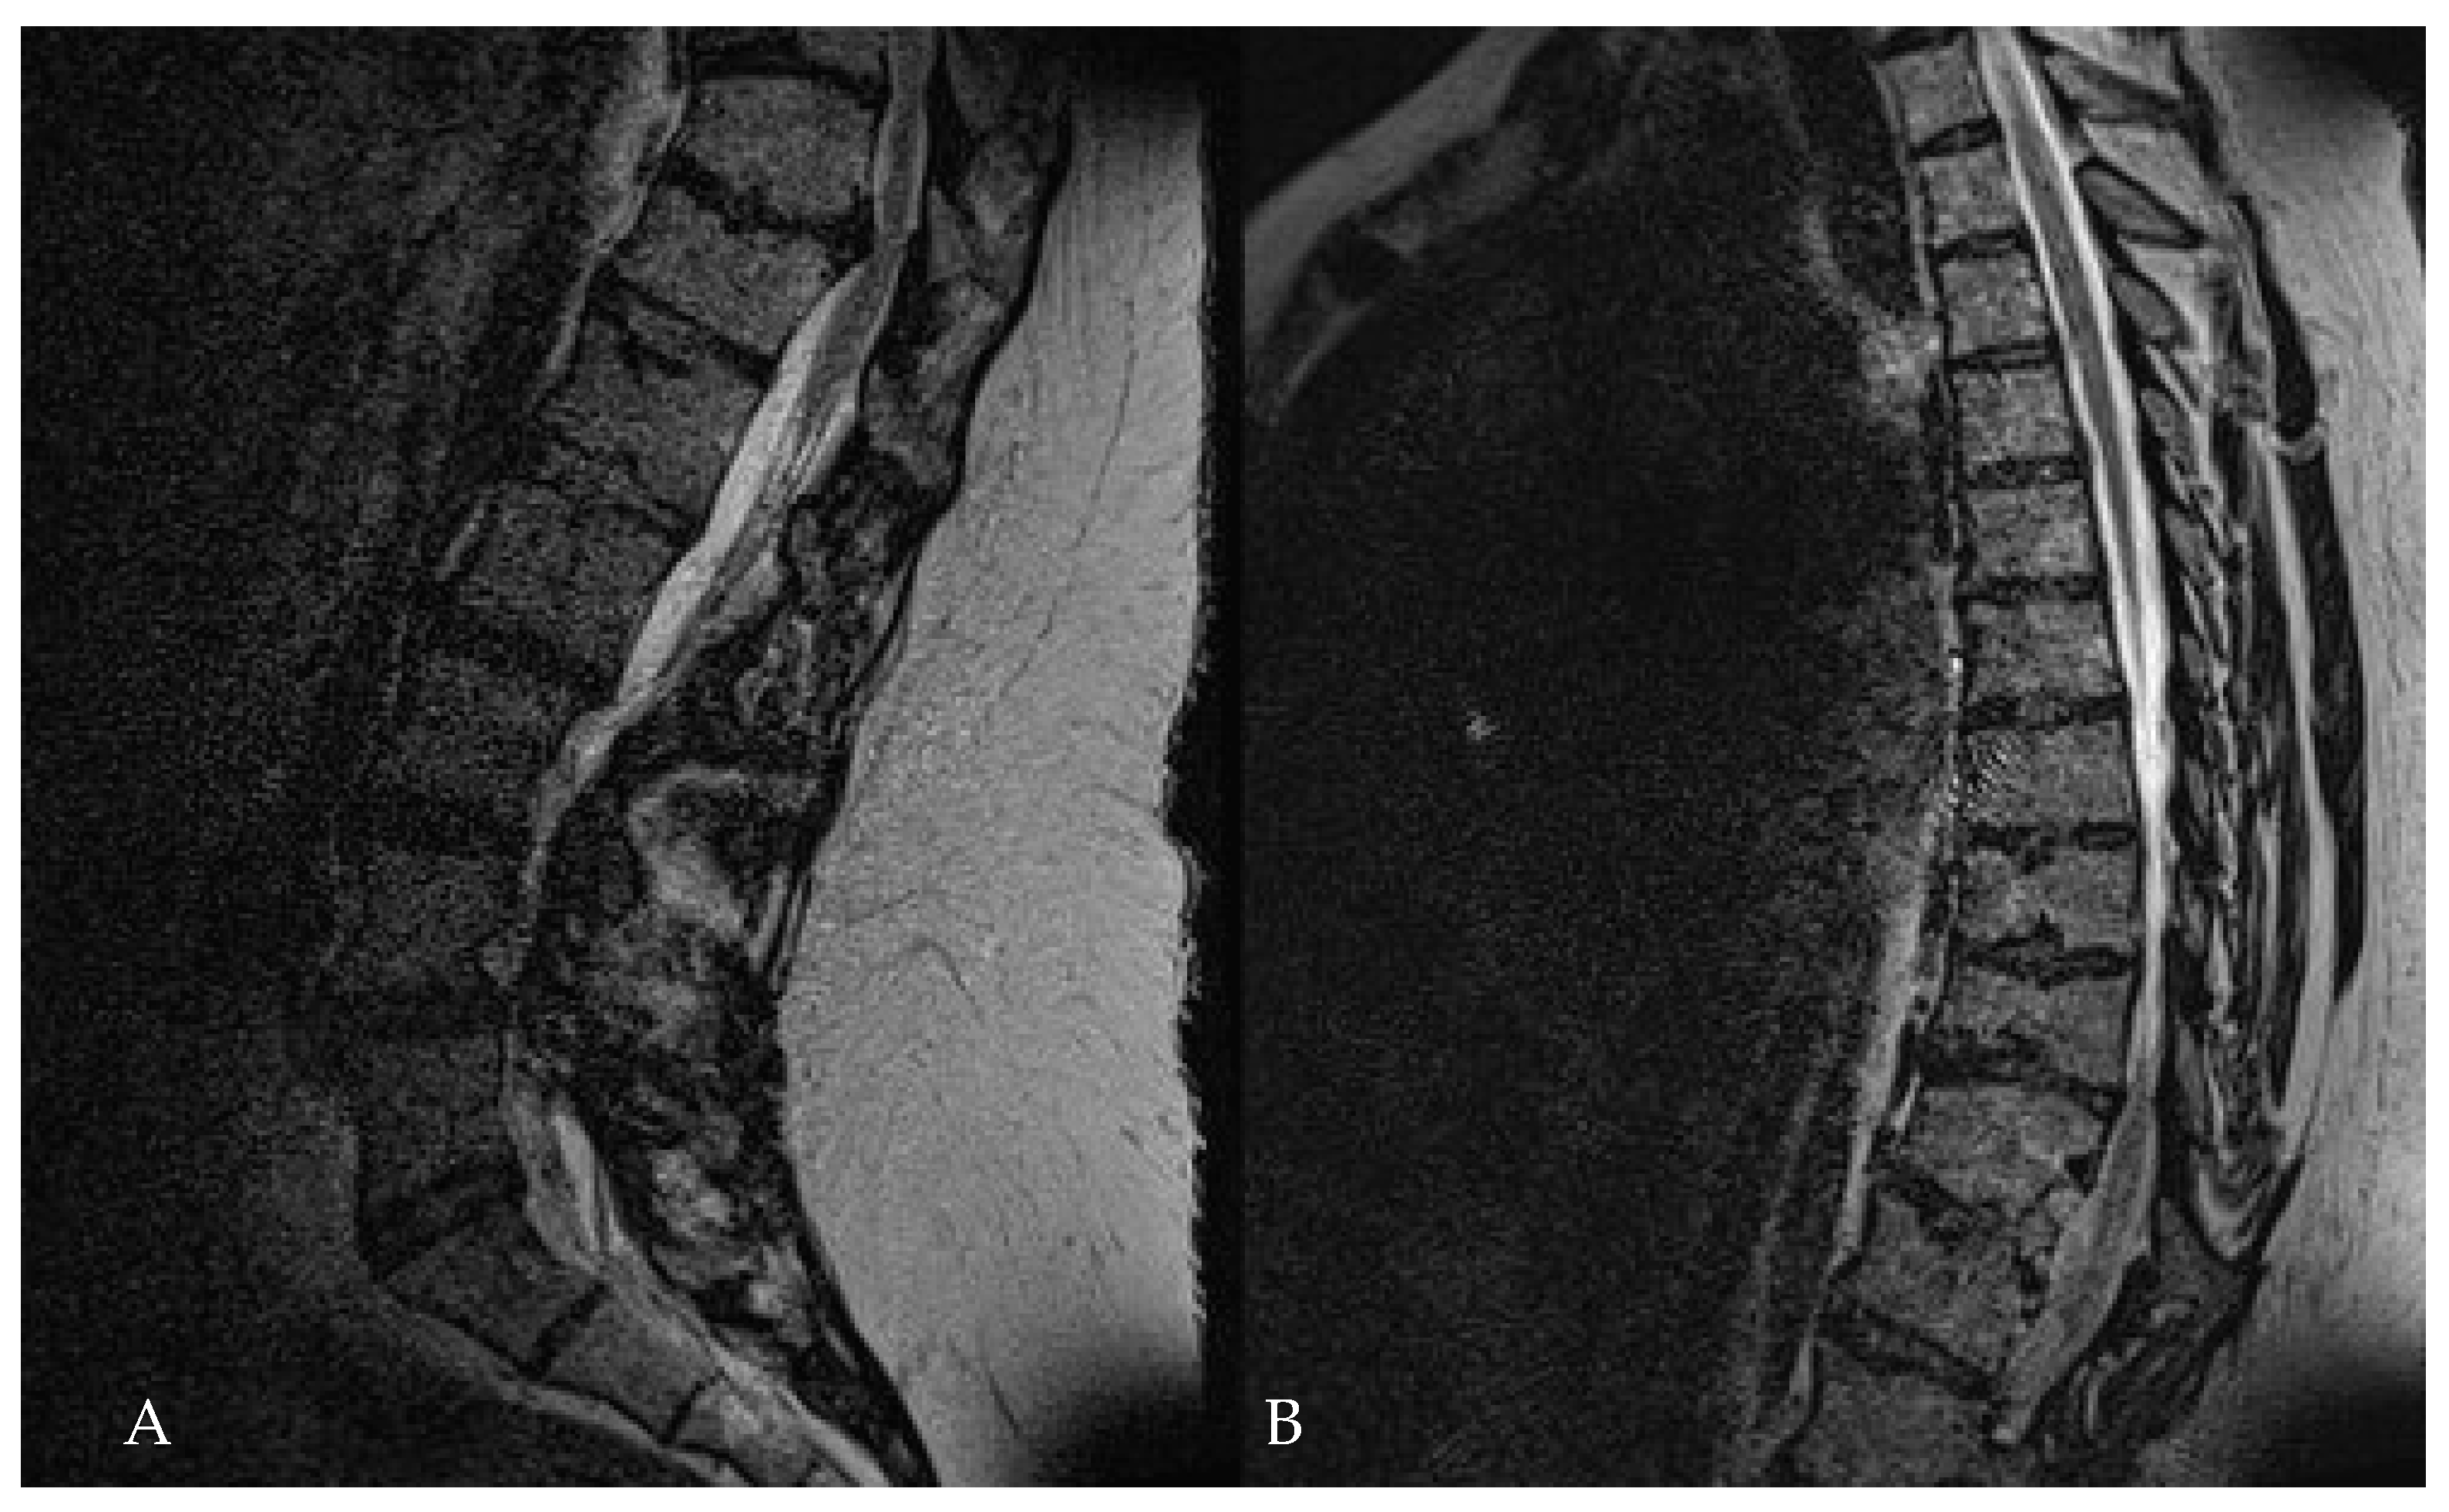

- Yuan, L.; Chen, Z.; Liu, Z.; Li, W.; Sun, C.; Liu, X. Clinical and radiographic features of adult calcified thoracic disc herniation: A retrospective analysis of 31 cases. Eur. Spine J. 2023, 32, 2387–2395. [Google Scholar] [CrossRef] [PubMed]

- Cornips, E.M.; Janssen, M.L.; Beuls, E.A. Thoracic disc herniation and acute myelopathy: Clinical presentation, neuroimaging findings, surgical considerations, and outcome. J. Neurosurg. Spine 2011, 14, 520–528. [Google Scholar] [CrossRef] [PubMed]

- Quraishi, N.A.; Khurana, A.; Tsegaye, M.M.; Boszczyk, B.M.; Mehdian, S.M. Calcified giant thoracic disc herniations: Considerations and treatment strategies. Eur. Spine J. 2014, 23 (Suppl. S1), S76–S83. [Google Scholar] [CrossRef] [PubMed]

- Barbanera, A.; Serchi, E.; Fiorenza, V.; Nina, P.; Andreoli, A. Giant calcified thoracic herniated disc: Considerations aiming a proper surgical strategy. J. Neurosurg. Sci. 2009, 53, 19–25, discussion 25–26. [Google Scholar] [PubMed]